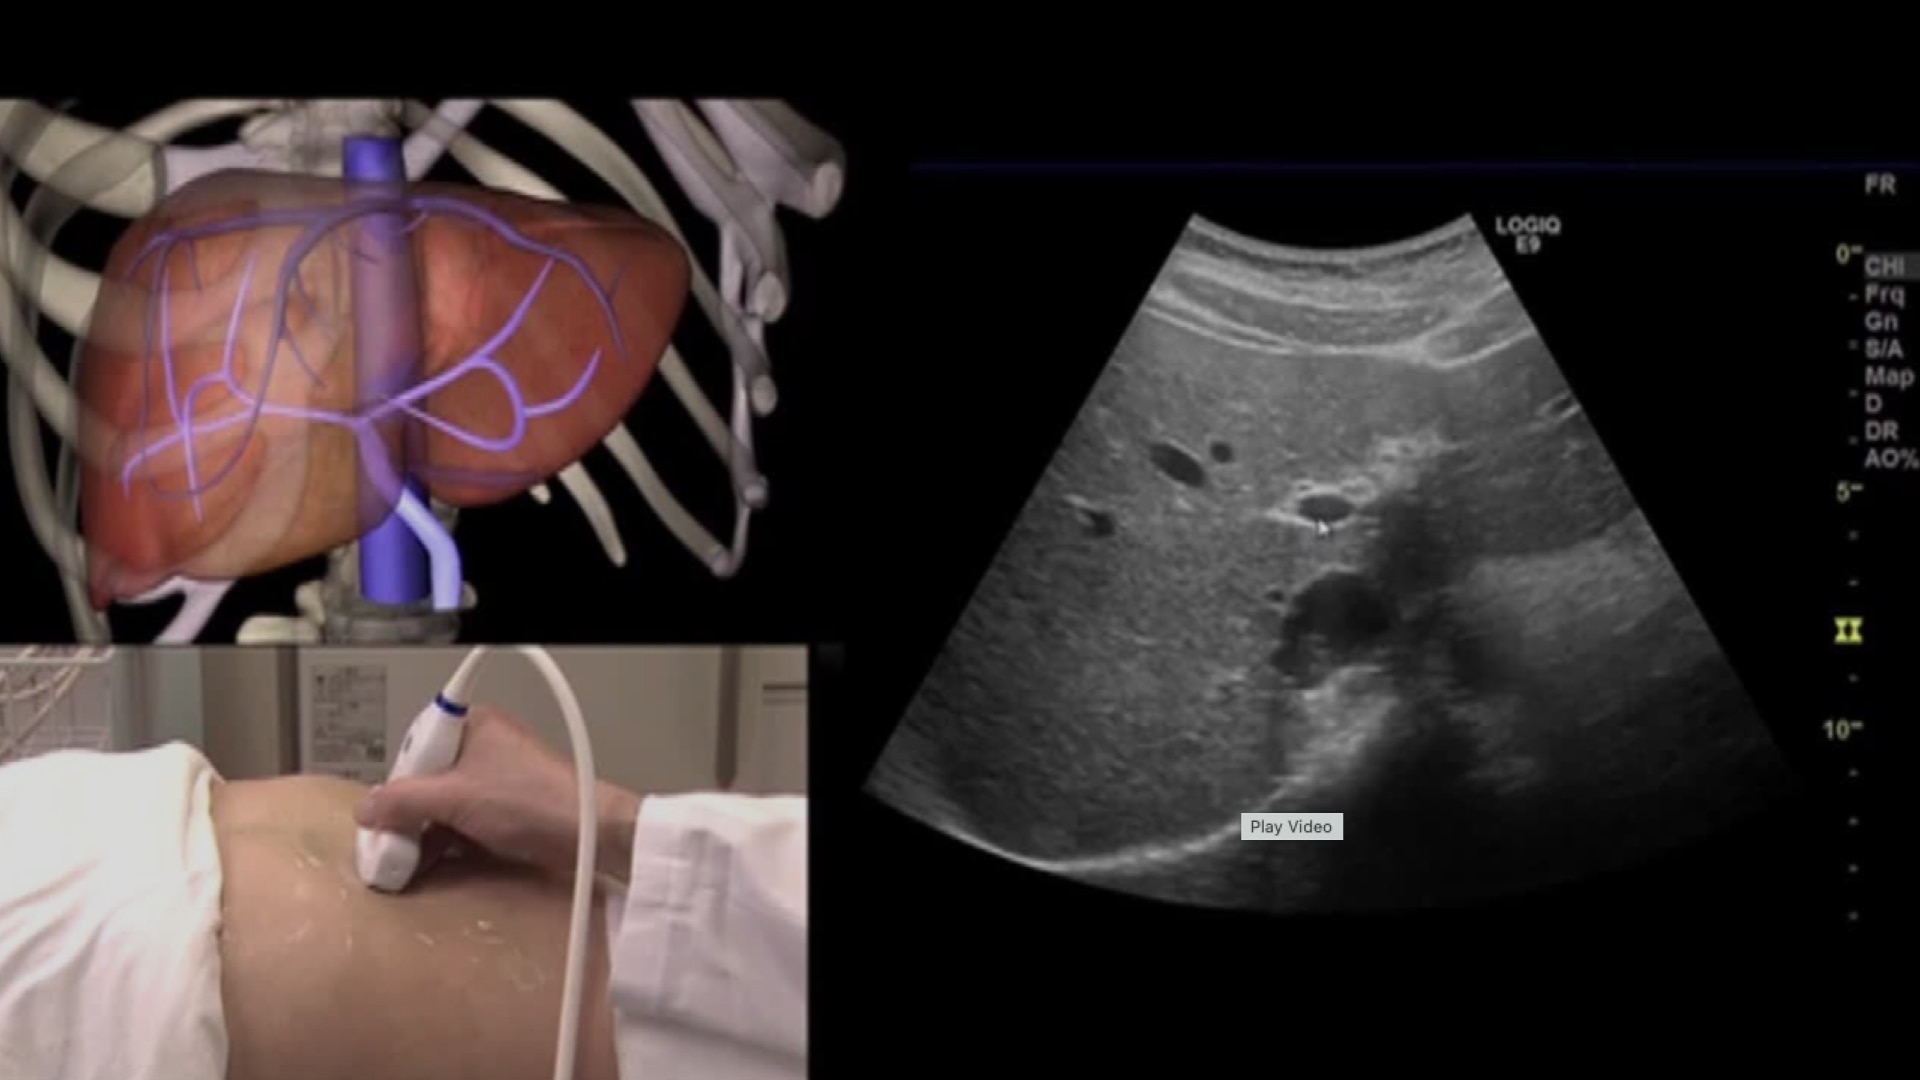

腹部超音波テキスト: 上・下腹部 (Atlas series) | 文雄, 辻本。腹部超音波テキスト 上・下腹部 改訂版 ベクトル・コア - メルカリ。腹部超音波テキスト〜上・下腹部〜 改訂第三版 (Atlas Series超。専用 水出しアイスティー トロピカルフルーツ 水出し アイスティー リプトン。Liver | GE HealthCare (Japan)。。2025年最新】腹部超音波テキスト 上 下腹部の人気アイテム。学校では教えてくれない腹部超音波のABC〜府中病院「超音波検査。腹部超音波テキスト 上下腹部 上下腹部 Atlas Series。Amazon.co.jp: 腹部超音波検査ドリル : 土居忠文, 上田彩未: 本。Screening | GE HealthCare (Japan)。「腹部超音波テキスト : 上・下腹部」辻本 文雄 / 井田 正博定価: ¥ 13000裁断済の商品になるので、傷汚れありにしています。腹部超音波テキスト〜上・下腹部〜 改訂第三版 買取価格|古本。裁断機でおこなっておりますので、それなりに綺麗かと思いますが、素人裁断になりますので、その点はご了承ください。中古品になるので、経年変化等もあるかもしれません。m3電子書籍 | 日超検 腹部超音波テキスト 第3版。見逃しがございましたら、申し訳ございません。気になる方はご遠慮ください。一般社団法人日本超音波検査学会 eラーニング。#辻本文雄 #辻本_文雄 #井田正博 #井田_正博 #本 #自然/医療・薬学・健康